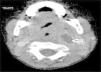

Se han recuperado estudios de imagen de 63 pacientes, a los que se les realizaron 71 pruebas. Las técnicas utilizadas han sido 36 TAC (50,7%), 20 ecografías (28,2%), 8 radiografía lateral de cuello (11,3%) y 7 RMN (9,9%). Al 62,5% (5 de los 8) de los que se realizó radiografía lateral de cuello y al 15% (3 de los 20) de los pacientes a los que se les realizó ecografía, hubo que completarles el estudio con TAC o RMN. A los pacientes a los que se les realizó TAC o RMN no hubo que hacerles más pruebas de imagen. La TAC ha sido empleada fundamentalmente en ACPI de localización más profunda (ARF, APA y APF), mientras que la ecografía fue empleada en ACPI más superficiales (AA y AS) (figs. 1 y 2).

Las técnicas de imagen más utilizadas han sido la TAC y la ecografía, empleadas en un 86% de los casos. Se usó cada una en diferente situación: la TAC preferentemente en abscesos de localización profunda y la ecografía en abscesos superficiales. La TAC se ha usado en el 100% de los APF y en el 75% de los ARF. La ecografía se usó en el 78% de los AS y en el 70% de las AA, siendo, no obstante, la prueba inicial en muchos casos con objeto de evitar radiaciones innecesarias a niños de corta edad14. Aunque la TAC supone una prueba que requiere colaboración del paciente (puede precisar sedación) e implica radiación del niño, en nuestra opinión es la prueba de elección ante ACPI de localización profunda, si hay mala respuesta al tratamiento o ante la sospecha de complicaciones y es, además, la herramienta más útil para la planificación de la cirugía3–5. La radiografía lateral de cuello, bastante utilizada en los servicios de urgencias, se ha usado solo en 8 ocasiones, todas en ARF, y en nuestro caso con una clara tendencia a la disminución en su uso. Por otro lado, en los últimos años estamos empleando más la RMN tanto como herramienta diagnóstica como para control radiológico ante la sospecha de persistencia de un ACPI tras la cirugía, evitando así radiaciones a los niños.